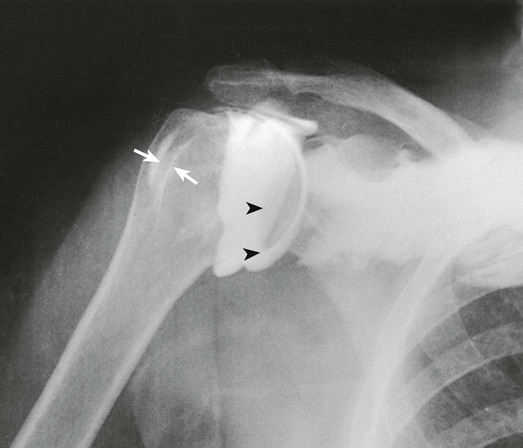

Arthrography of the shoulder is performed primarily for the evaluation of partial or complete tears in the rotator cuff or glenoid labrum, persistent pain or weakness, and frozen shoulder. A single-contrast technique (Fig. 12-4) or a double-contrast technique (Fig. 12-5) may be used.

For a single-contrast arthrogram (Fig. 12-6), approximately 10 to 12 mL of positive contrast medium is injected into the shoulder. For double-contrast examinations, approximately 3 to 4 mL of positive contrast medium and 10 to 12 mL of air are injected into the shoulder.

The projections most often used are the AP (internal and external rotation), 30-degree AP oblique, axillary (Figs. 12-7 and 12-8), and tangential. (See Volume 1, Chapter 5, for a description of patient and part positioning.)

After double-contrast shoulder arthrography is performed, computed tomography (CT) may be used to examine some patients. CT images may be obtained at approximately 5-mm intervals through the shoulder joint. In shoulder arthrography, CT has been found to be sensitive and reliable in diagnosis. Radiographs and CT scans of the same patient are presented in Figs. 12-5 and 12-9. Shoulder arthrography is increasingly performed with MRI, with injection of gadolinium contrast media into the joint capsule (Fig. 12-9, B).